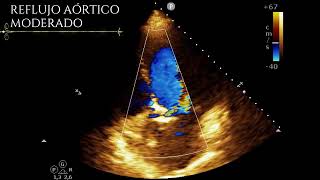

Tiempo de hemipresión en insuficiencia aórtica